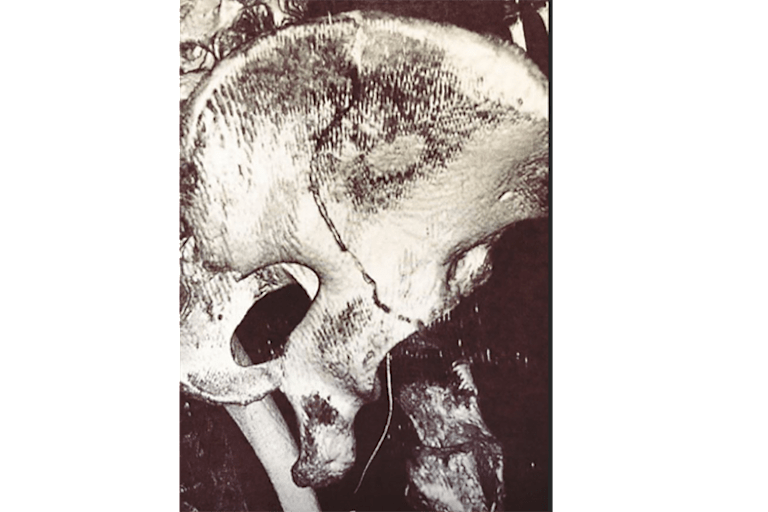

Der nächste Rückschlag für den leidgeprüften Dominique Aegerter. Der Schweizer aus dem Team Kiefer Racing kam am Donnerstag beim Enduro-Training zu Sturz und zog sich dabei eine längere Fissur (Riss) in der rechten Beckenschaufel zu.

Bei einem an sich harmlosen Sturz fiel er unglücklich seitlich auf einen Stein und musste sofort zu weiteren Untersuchungen ins Inselspital Bern überführt werden. Der 27-jährige Oberaargauer hatte Glück im Unglück, denn es liegt nach aktuellem Stand kein verschobener Bruch vor. Trotzdem wird Aegerter zur Beschleunigung des Heilungsprozesses noch am Freitag oder am Samstagmorgen operiert. Aegerter wird somit nicht am nächsten Grand Prix im spanischen Jerez de la Frontera (6. Mai) teilnehmen können.